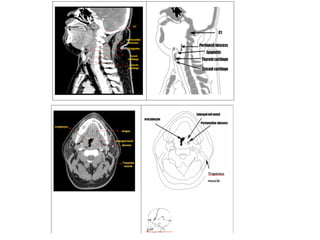

Obstruction of upper airways

Contributing factors

• Contributing factors in the obstruction of

upper airways include: anatomical airway

constriction, developmental anomalies,

macroglossia, enlarged tonsils and adenoids,

nasal polyps and allergic rhinitis.

• Enlarged adenoids as the major contributing

factor.

• Airway obstruction, resulting from nasal cavity

or pharynx blockage, results in postural

modifications such as open lips, lowered

tongue position, anterior and posteroinferior

rotation of the mandible, and a change in

head posture. These modifications take place

in an effort to stabilize the airway.